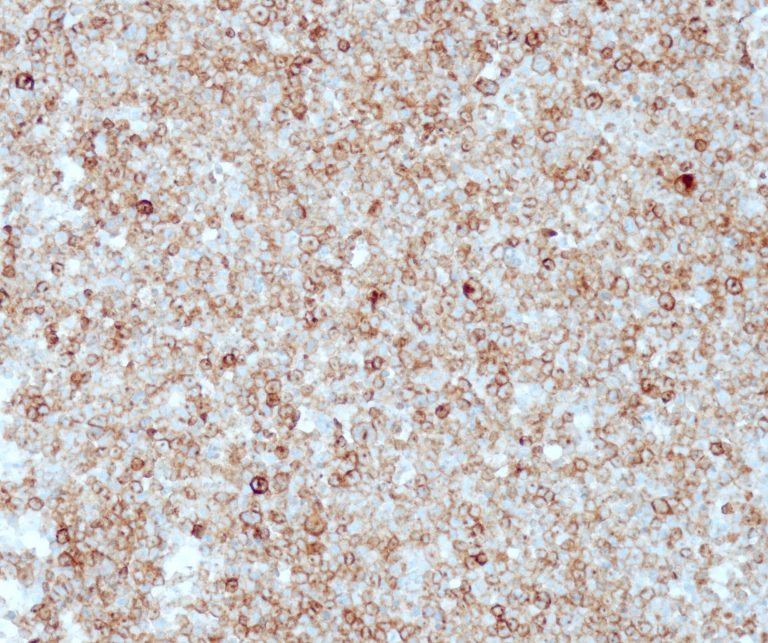

Vascular Pathology

Gastrointestinal (GI) Pathology

General Marker

Breast Pathology

Endocrine Pathology

Gynecological Pathology

Neuropathology

Infection Markers

Lung Pathology

Urinary Tract Pathology

Transplantation Pathology

Soft Tissue Pathology

Hematopathology